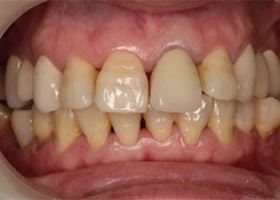

治療前全口X光片、口內正面照片。

治療前門牙特寫、切端特寫照,發現假牙略微暴牙。